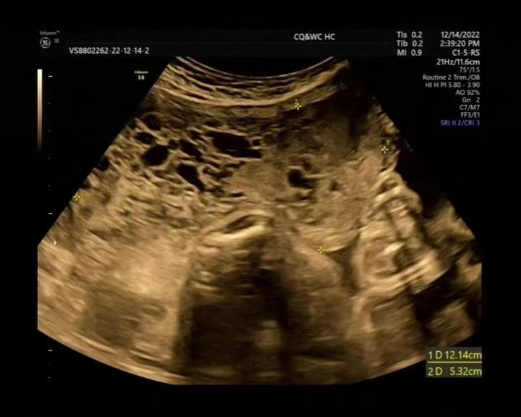

重庆市妇幼保健院--产科病例专栏 本期病例由王岚主任团队提供。王岚主任团队从事妇产科围产保健临床医疗工作多年,具有丰富的临床经验,希望通过病例分享能对广大妇产科同仁有所帮助,共同进步。 病例详情 患者,女,汉族,28岁,已婚,0-0-0-0,外院促排卵后自然受孕,因“停经30周,全身皮肤瘙痒2+天”入院。 现病史:LMP:2022-05-29,EDC:2023-03-06。孕期定期于外院产检。孕早期彩超提示:宫内双胎(双绒双羊)。NT1.4/1.4mm,无创基因筛查低风险;系统超声及胎儿心脏彩超未做。中孕期OGTT:5.22-9.78-9.03mmol/L,诊断为妊娠期糖尿病,予饮食运动控制,未正规监测血糖。孕23+5周因“妊娠期肝内胆汁淤积症(重度)”于外院住院,予降胆酸、促胎肺成熟等对症治疗,住院期间监测血压高(血压波动在138-170/80-103mmHg),考虑“子痫前期(重度)”,遂于孕24+3周于外院转入我院继续治疗。转入我院后行彩超提示:“乙胎儿胎盘超声所见:考虑胎盘间叶发育不良?部分性葡萄胎?”,考虑妊娠合并部分性葡萄胎可能,建议行羊水穿刺,孕妇及家属拒绝,予拉贝洛尔片200mg tid+硝苯地平控释片30mg bid降压后血压控制好,予口服熊去氧胆酸胶囊250mg po tid降胆汁酸降至正常,之后定期我院门诊产检。孕27+5周复查彩超示:乙胎儿超声孕周小于临床孕周;心胸比增大,乙胎儿部分胎盘呈蜂窝状改变:考虑胎盘间叶发育不良?部分性葡萄胎?再次建议羊水穿刺,孕妇及家属仍拒绝。孕29+5周全身皮肤瘙痒明显,于30周查空腹肝功示:ALT 238U/L、AST 117U/L、TBA 51.4umol/L,遂以“1.子痫前期(重度) 2.妊娠期肝内胆汁淤积症(重度) 3.双胎妊娠(双绒双羊) 4.胎儿生长受限(乙胎)?5.妊娠30周孕1产0LO/RO待产”收入我院。 既往史:无特殊。 生育史:初婚,0-0-0-0。 查体:体温:36.5℃,脉搏:93次/分,呼吸:20次/分,血压:129/66mmHg,身高150cm,体重57.5Kg。心肺(-)。腹膨隆。 专科情况:宫高36cm,腹围90cm,先露头/头,胎方位LO/RO,胎心140/145次/分,律齐,未扪及明显宫缩,阴道检查:宫口未开,胎儿体重估计1100/800g左右。 辅助检查:2022年12月21日我院彩超:双顶径7.37/6.44cm 头围26.19/23.85cm 腹围23.14/21.09cm 股骨长5.16/4.76cm 羊水最大深度5.40/3.40cm 胎心有/有脐动脉S/D 2.71/3.89。乙胎(位于右上):胎盘:位于右底前壁,部分胎盘实质呈蜂窝状改变,范围约12.14x5.32cm,成熟度:I+,厚度约4.4cm。乙胎儿双顶径(-3.0SD),头围(-4.0 SD),腹围(-3.3 SD),股骨长(-2.5 SD)。乙胎儿心胸比:0.33。双胎间体重差约24%。 入院诊断 1.妊娠期肝内胆汁淤积症(重度) 2.双胎妊娠(双绒毛膜双羊膜囊) 3.子痫前期(重度) 4.妊娠期糖尿病A1级 5.胎儿生长受限(乙胎)? 6.部分性葡萄胎(乙胎)? 7.妊娠30周孕1产0LO/RO待产